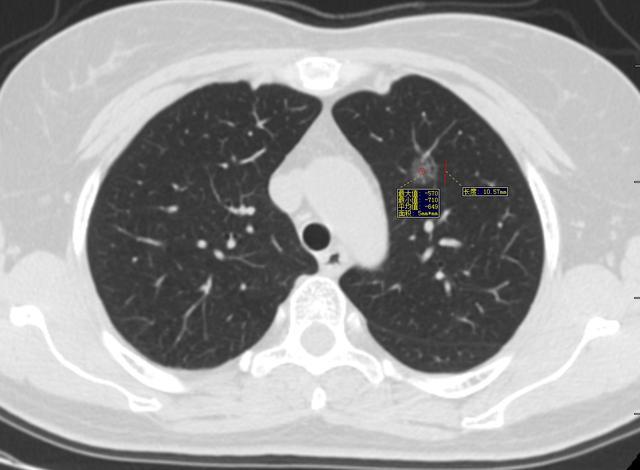

图1、2004年

图2、3 2008年1月10日

图4 2015年4月29日

图5、6 2020年5月15日

漫长的16年,一个纯磨玻璃结节从原位腺癌缓慢正常到浸润性腺癌早期阶段(影像估测),所以说纯磨玻璃结节是不可怕的,可以安心随访,到合适的时机手术完全来得及,不要上来动不动就手术,动不动就消融!